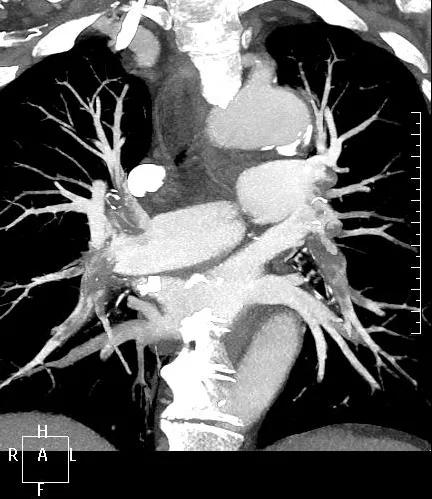

近日,一名港胞翁阿姨在我市突發(fā)急性肺栓塞,生命垂危。市二院在接到120出車指令后,迅速響應(yīng),患者入院后開通綠色通道,經(jīng)急診科、心內(nèi)科、介入科、重癥醫(yī)學(xué)科等多學(xué)科專家開展聯(lián)合會診,并于當(dāng)晚9點行“下腔靜脈、肺動脈造影+導(dǎo)管溶栓+濾器植入術(shù)”,患者終于轉(zhuǎn)危為安,經(jīng)后續(xù)治療與精心護(hù)理,病情逐漸穩(wěn)定,現(xiàn)已轉(zhuǎn)入普通病房。